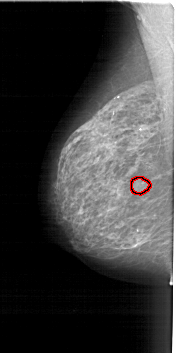

A_1784_1.LEFT_MLO

LEFT_MLO LINES 6346 PIXELS_PER_LINE 3151 BITS_PER_PIXEL 12 RESOLUTION 43.5 OVERLAY

FILE: A_1784_1.LEFT_MLO.OVERLAY

TOTAL_ABNORMALITIES 1

ABNORMALITY 1

LESION_TYPE MASS SHAPE LOBULATED MARGINS ILL_DEFINED

ASSESSMENT 4

SUBTLETY 4

PATHOLOGY BENIGN

TOTAL_OUTLINES 1

BOUNDARY